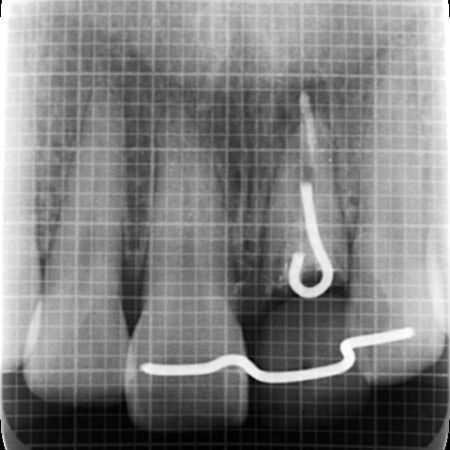

またレントゲン撮影をして詳しく検査したところ、左上前歯が細菌感染を起こしており、歯根の先端に膿が溜まっていることが判明しました。歯の土台となっている金属のメタルコアも、長期保存が不可能な状態です。

そのうえで、まずは歯茎の位置をほかの歯とそろえるために歯根を引っ張り出す部分矯正であるエクストリュージョン(歯根挺出術)を行い、その後抜歯をする治療方法を提案し、同意いただきました。

まずは左上前歯にエクストリュージョンを行い、歯と歯茎の境目を整えたうえで抜歯を行います。抜歯と同時にインプラントを埋め込み、治療中の審美性を考慮して仮歯を装着しました。